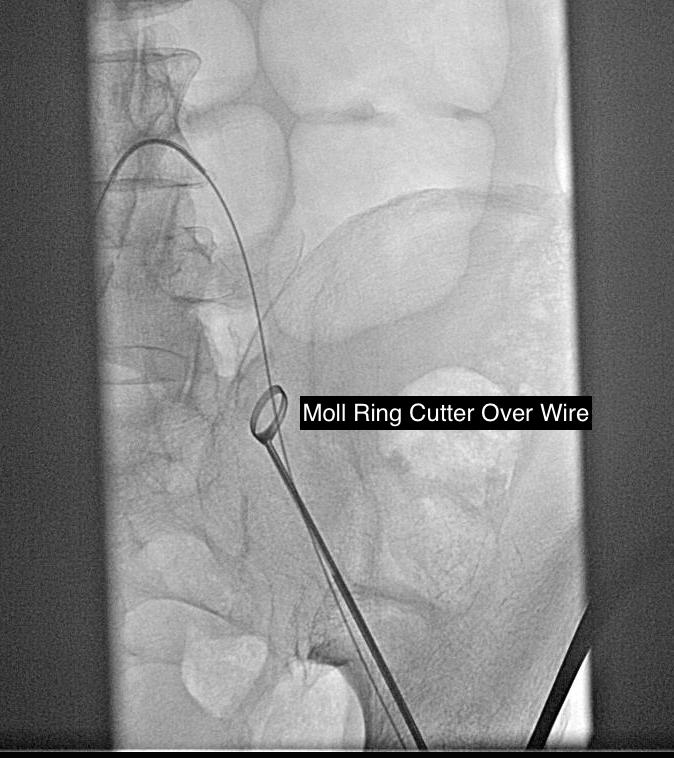

The common femoral endarterectomy is done from its distal most point and the Vollmer ring is used to mobilize the plaque. A Moll Ring Cutter (LeMaitre Vascular) is then used to cut the plaque.

Remote endarterectomy is a bit of a lost art from the early days of vascular surgery. A ring dissector (Vollmer Ring Dissector, LeMaitre Vascular) is used to liberate the plaque from the remnant adventia. A cutting device (Moll Ring Cutter, LeMaitre Vascular) shown third from left below is used to divide the plaque.